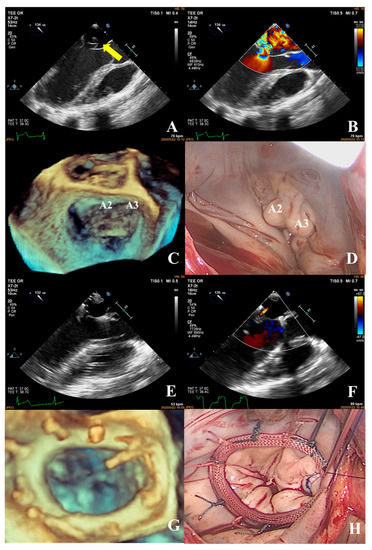

- The most common pathogenesis in the intermediate group was mitral valve prolapse involving multiple segments, with or without ruptured chordae tendineae. Mitral valve prolapses most often involved the posterior leaflet, specifically the P2 segment [17,19,22]. A patient with mitral valve prolapses involving the A1, A2, and A3 segments but no rupture of chordae tendineae had a complexity score of 7 (3 × 2 + 1) and a surgical technique score of 5 (2 × 1 + 1). The prolapsed leaflets were processed to reconstruct the artificial chordae tendineae and suture the sector junction to provide enough support when the leaflets were closed, thus increasing the coaptation area to reduce regurgitation (Figure 8).